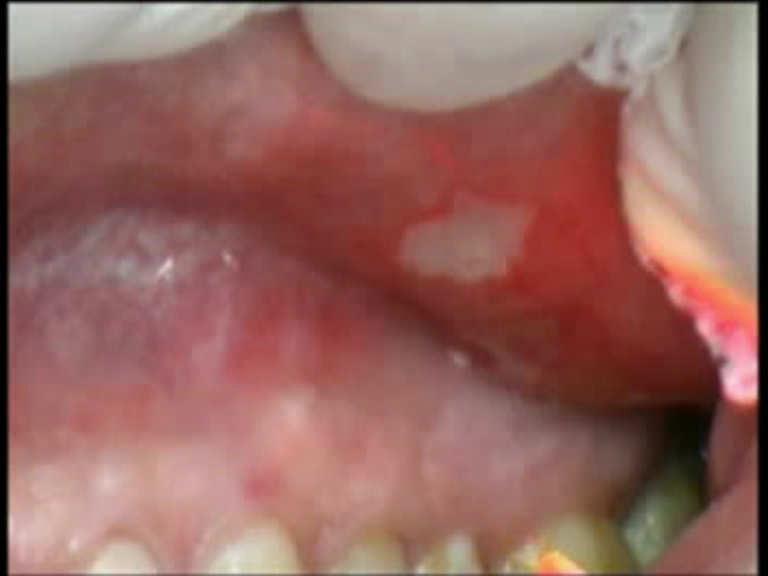

The aphthas treatment can have different lasers applications. In the upper case, the aphthas surface was removed with pulsed setting, while the case 1 and 3 the aphtha was dried up with without touch.